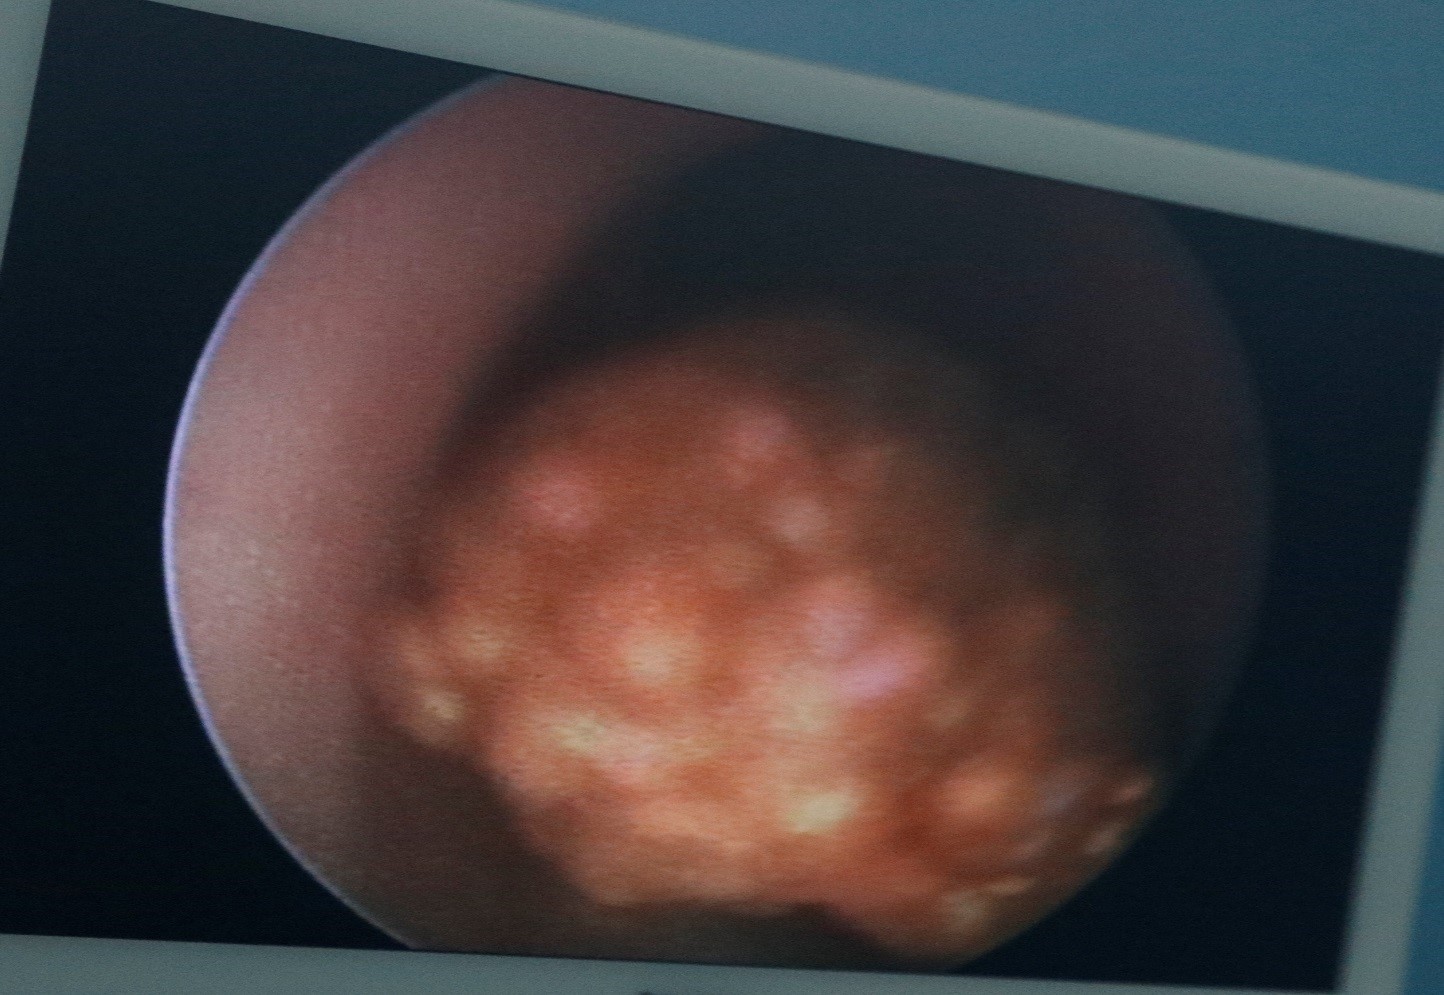

Ảnh. Viên sỏi niệu quản của bệnh nhân được phát hiện